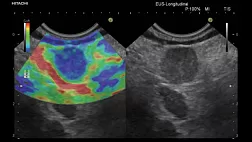

Эндоцитоскопия является одним из наиболее интенсивно развивающихся методов эндоскопической диагностики, позволяющим исследовать слизистую оболочку, а, по данным ряда экспериментальных работ — строму и паренхиму различных органов, с увеличением изображения до 1100 раз.

• По разрешающей способности с ней может сравниться только конфокальная лазерная эндомикроскопия, обеспечивающая увеличение до 1000 раз.

• Преимуществом эндоцитоскопии над конфокальной лазерной эндомикроскопией является отсутствие необходимости внутривенного введения флуорофоров.

• Витальные красители, наносимые топически на слизистую оболочку, свободно доступны и безопасны.

• С появлением в ближайшем будущем новых эндоцитоскопов для исследования пищевода, желудка, толстой кишки и дыхательных путей можно ожидать значительного увеличения точности эндоскопической диагностики ранних форм рака и предраковых заболеваний вышеописанных органов.

• Уже в настоящее время, с нарастанием увеличения изображения, обеспечиваемого эндоскопической аппаратурой, наблюдается тенденция смещения традиционной эндоскопической диагностики в сторону морфологического исследования и для эффективного выполнения эндоцитоскопии врачу-эндоскописту, безусловно, необходимо изучать тканевое и клеточное строение стенки органов желудочно-кишечного тракта и дыхательных путей.